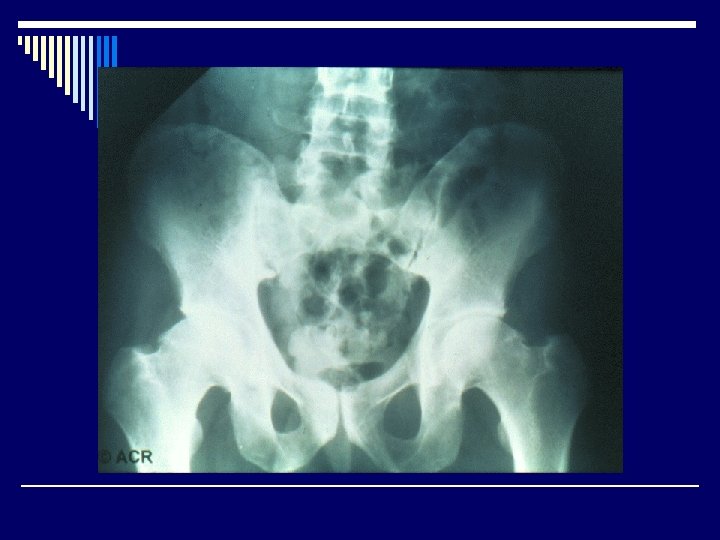

Radiological features o Joint effusion o Erosion o Joint space narrowing o Joint deformity o Osteoporosis o Bony ankylosis